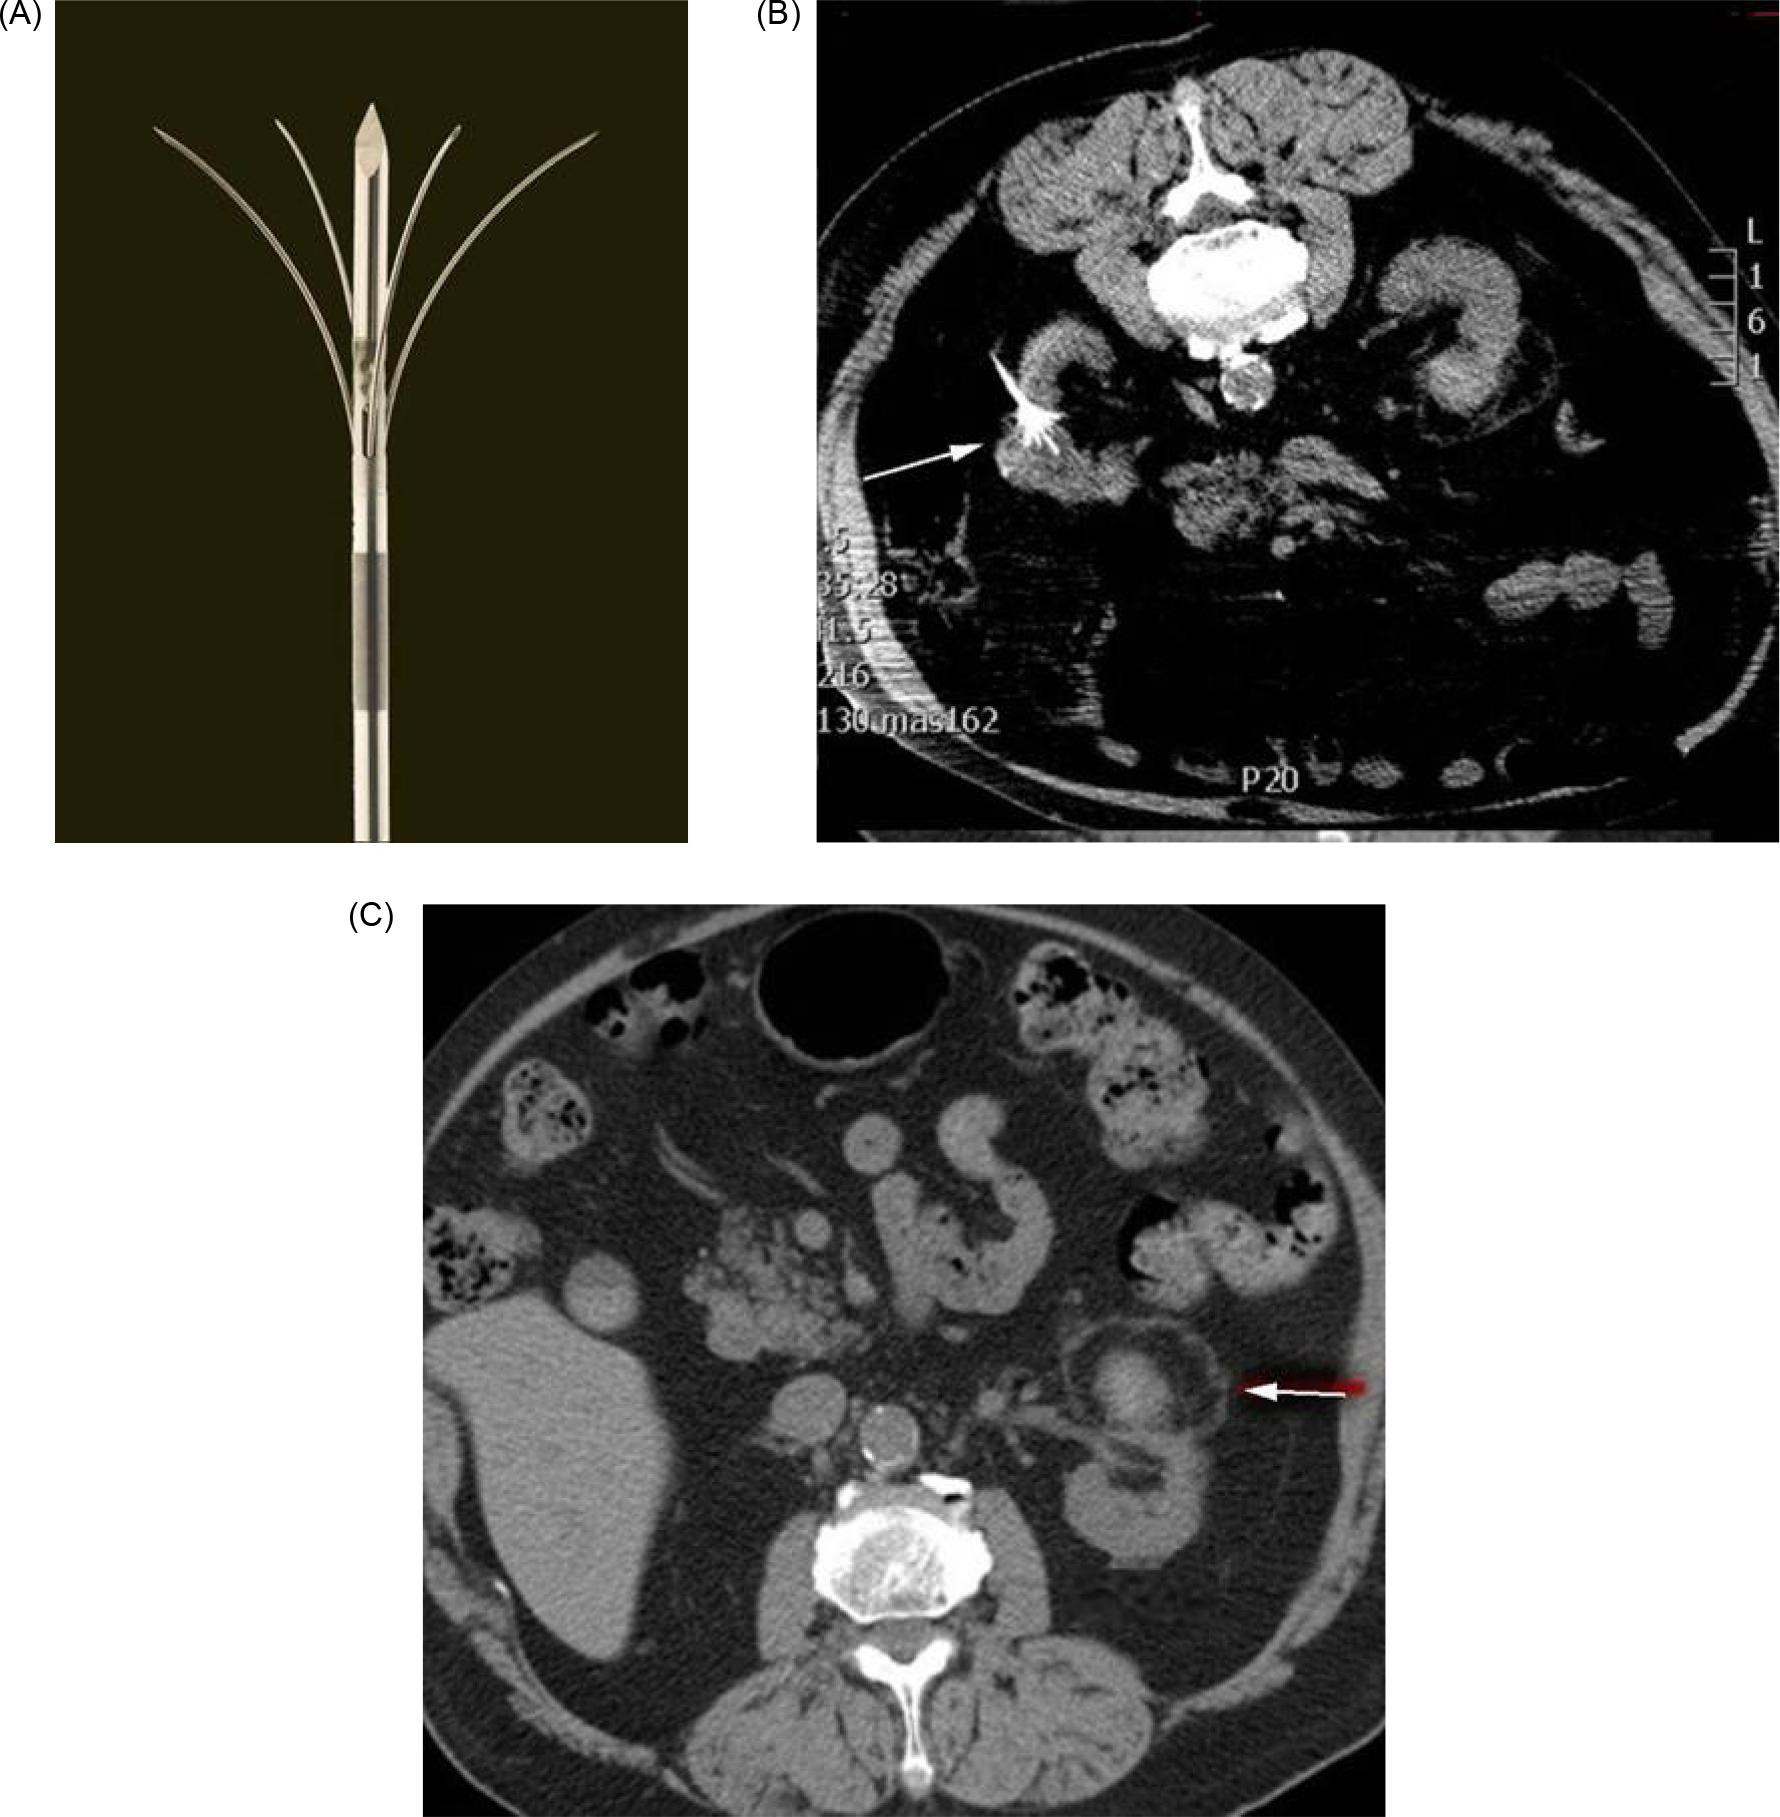

Radiofrequency ablation uses an electrical current in the radio frequency range, between 3 Hz and 300 GHz, to heat tissue resulting in coagulative necrosis. The alternating current is delivered through antennas placed directly into the tumor, with the electrical circuit completed through grounding pads, such as those seen with the Bovie cautery device (24). As current passes through the tissue, heat is generated due to tissue resistance, a concept termed “resistive heating” (Figure 2) (25). Cell death occurs instantly at temperatures above 60°. Notably, effective delivery of RFA relies on the electrical and thermal conductivity in tissue, which can be adversely affected by overheating and desiccation of the tissue directly adjacent to the electrode, resulting in an insulating barrier of charred tissue (26). RFA is often not recommended adjacent to large vasculature, due to inability to overcome the heat sink effect leading to increased risk of incomplete necrosis, possibly impacting oncologic efficacy (27). Over the years, a variety of techniques have been developed to monitor tissue temperature and impedance to limit desiccation and increase the zone of ablation (28). Similarly, multi-tined, expandable, and perfusion electrodes, and bipolar electrode systems are available technologies used to modulate the size and shape of the ablated tissue (26) (Figures 3A–3C).

Figure 3: (A) Multi-tined radiofrequency ablation antenna. (B) Radiofrequency ablation antenna expanded within tumor. (C) Typical tissue changes after successful radiofrequency ablation including pseudo-capsule, subcapsular fat, and nonenhancing lesion.